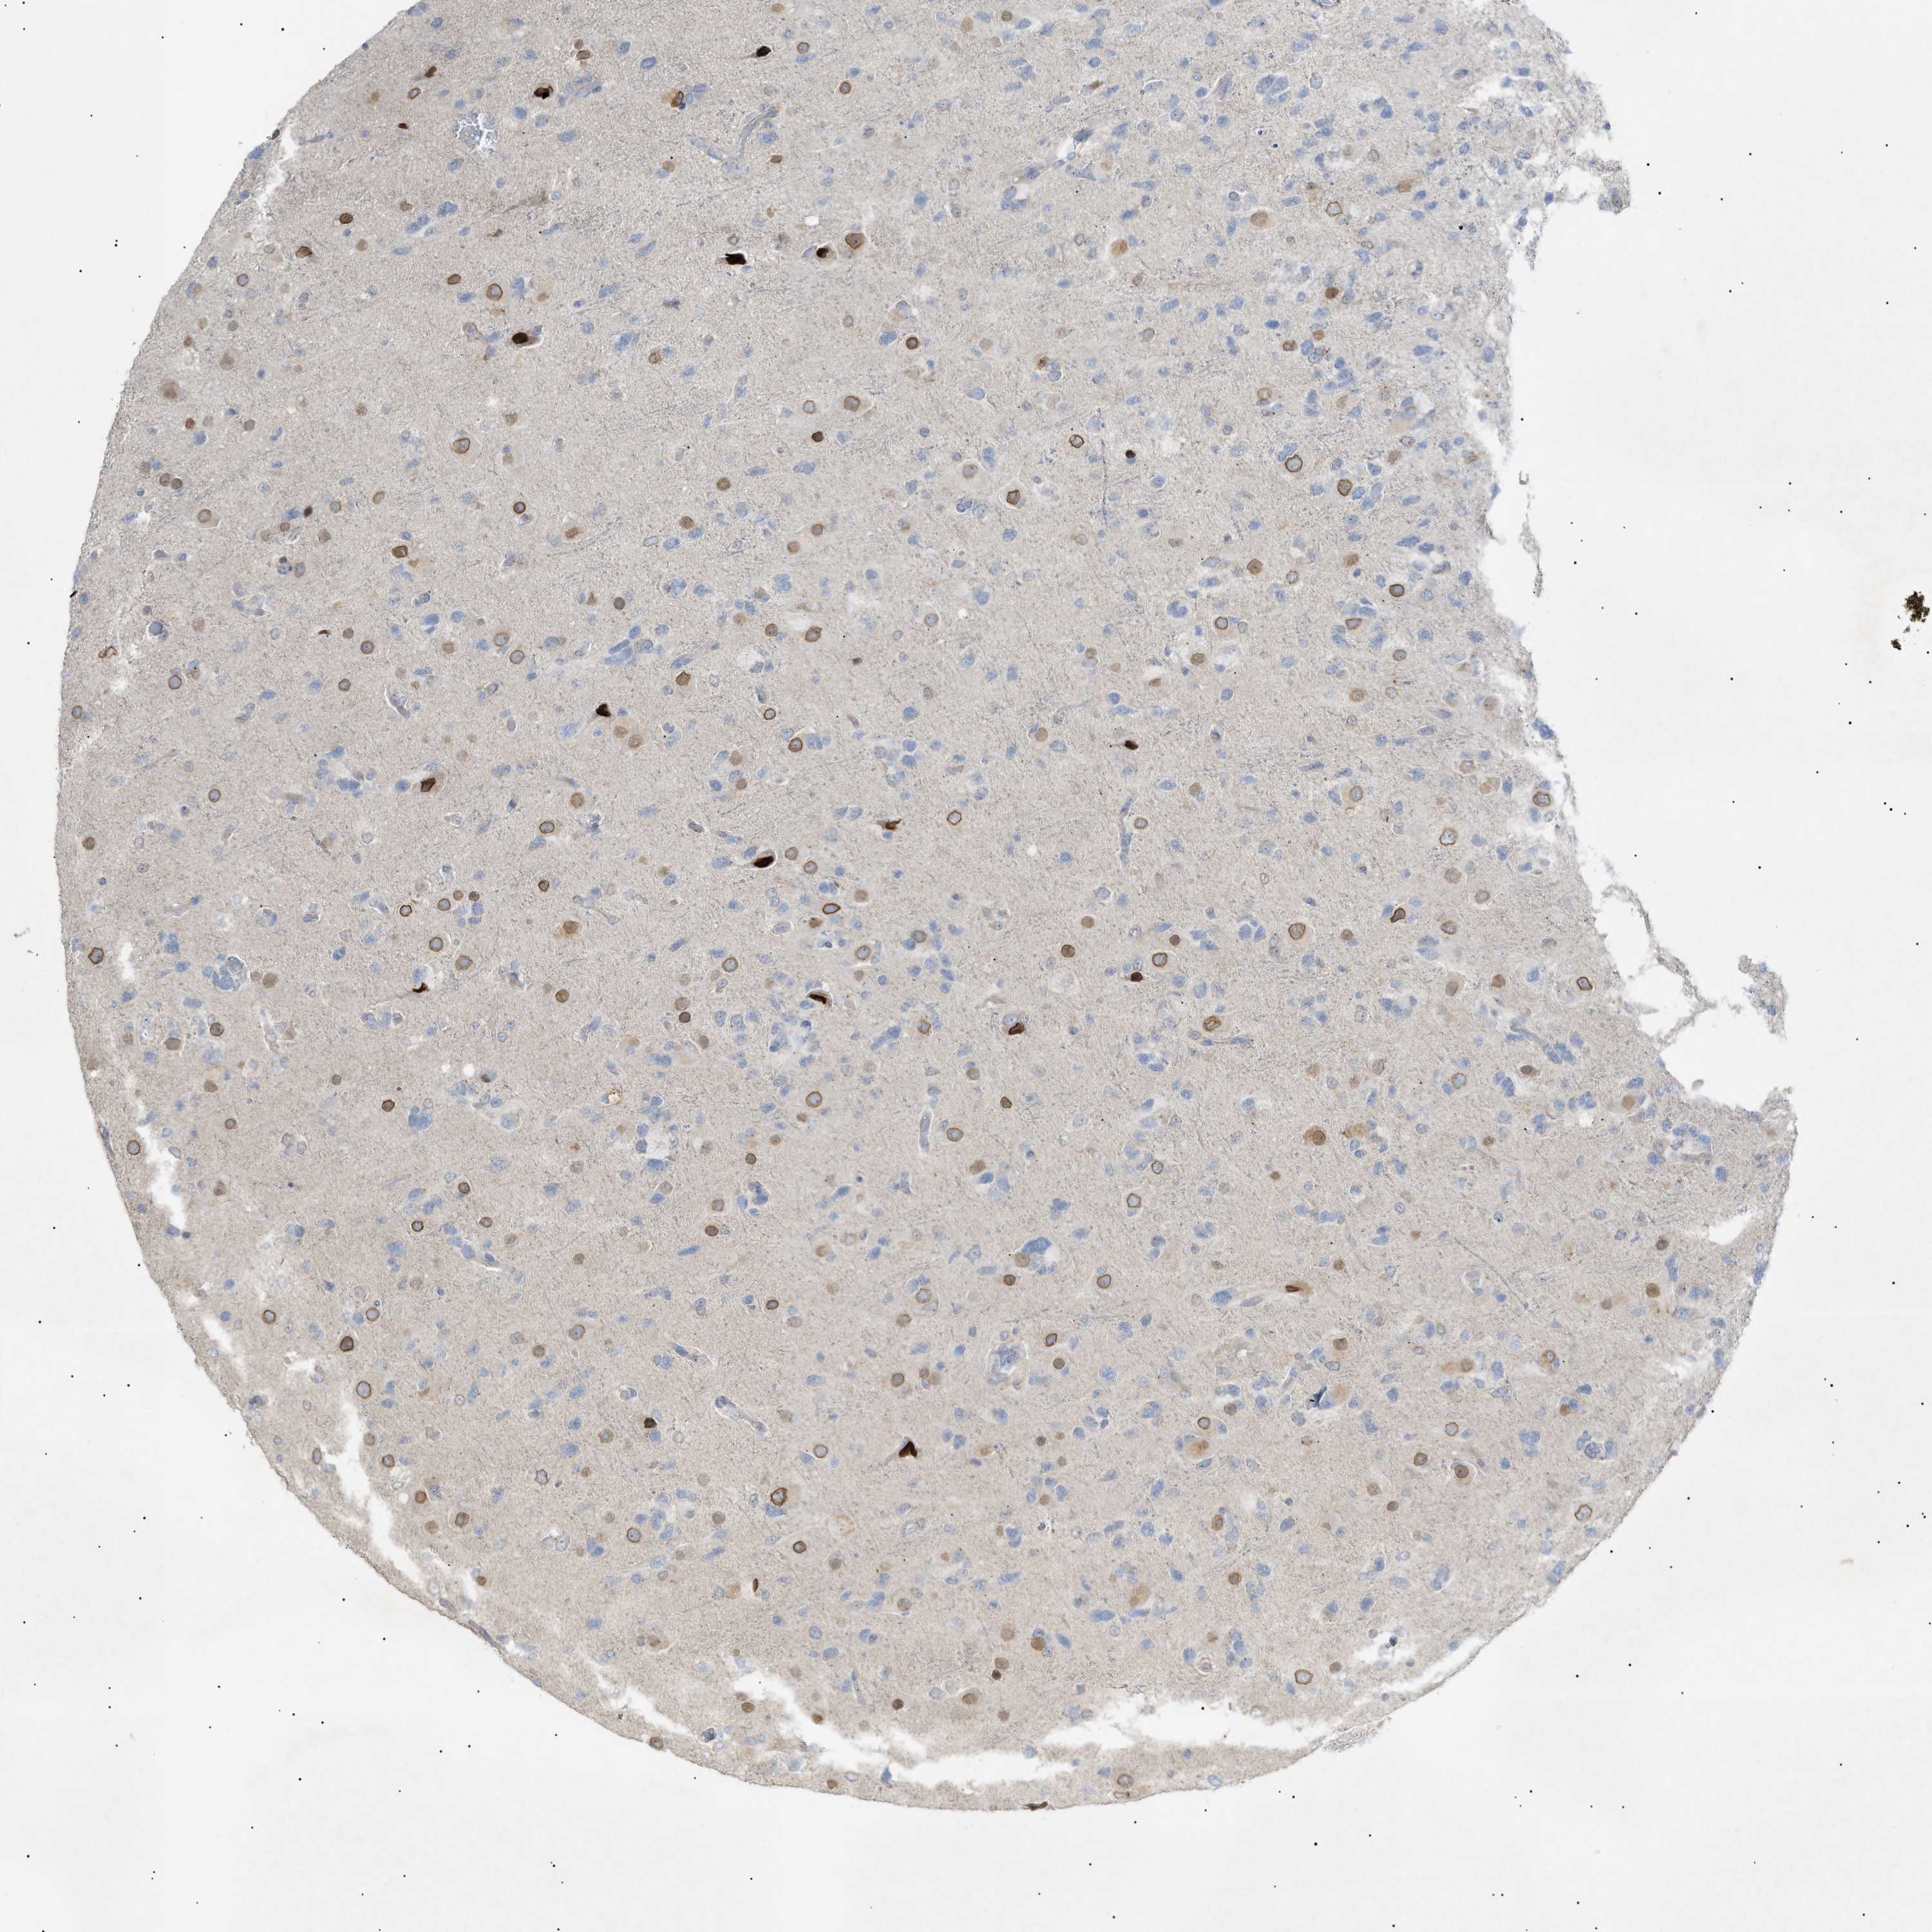

GLIOMA - Protein expressioni

A mouse-over function shows sample information and annotation data. Click on an image to view it in a full screen mode. Samples can be filtered based on level of antibody staining by selecting one or several of the following categories: high, medium, low and not detected. The assay and annotation is described here.

Note that samples used for immunohistochemistry by the Human Protein Atlas do not correspond to samples in the TCGA dataset.

Antibody stainingi

Antibody staining in the annotated cell types in the current human tissue is reported as not detected, low, medium, or high, based on conventional immunohistochemistry profiling in selected tissues. This score is based on the combination of the staining intensity and fraction of stained cells.

Each image is clickable and will lead to virtual microscopy that enables deeper exploration of all samples and also displays staining intensity scores, fraction scores and subcellular localization as well as patient and tissue information for each sample.

Antibody HPA015064

Antibody HPA071684

Glioma, malignant, High grade

Glioma, malignant, Low grade